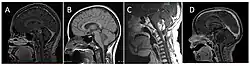

| Brain stem glioma. MRI axial, with contrast | |

Neuroimaging, such as MRI, is the main diagnostic tool for brain stem gliomas. In very rare cases, surgery and biopsy are performed.